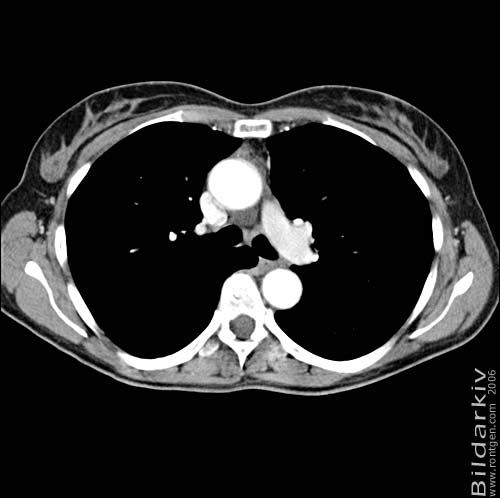

Thorax 24

Snitt över thorax med kontrast. Sk. mediastinum-fönstersättning.

CT Röntgen Helsingborgs lasarett

Mediastinum